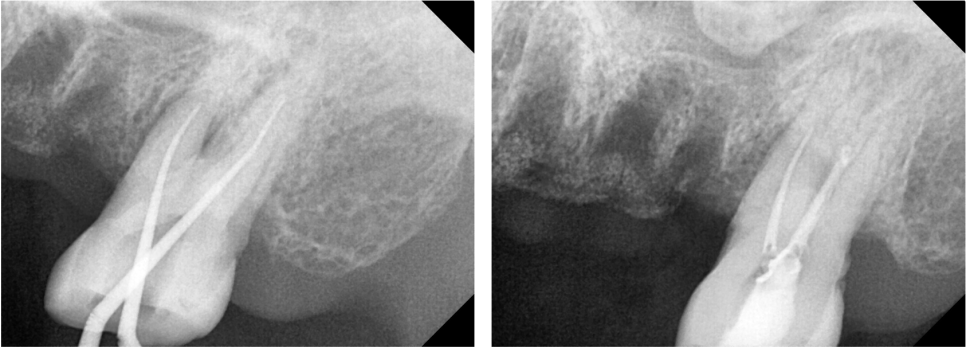

다수의 치아가 흔들리는 상황이였기에

치아의 뿌리를 조금 더 정밀하게 볼 수 있는

치근단 엑스레이와 CT를 추가적으로 촬영하였습니다.

치근단 엑스레이와 CT를 확인해본 결과

통증의 원인이 되는 큰어금니 하나는

뿌리쪽에서 뿌리 끝 염증이 생긴것을 확인했습니다.

이 뿌리 끝 염증이 커질수록 잇몸이 붓고

심하게는 뼈를 녹이게 되므로

주변 치아까지 영향을 미치게 됩니다.

뿌리에 생긴 낭이 뼈를 녹여

상악뼈 양이 얼마 남지 않은

모습을 확인할 수 있습니다.

상악동이라는 코 옆의 공기주머니는

아주 얇은 막으로 둘러싸여 있어서

혹시라도 찢어지거나 뚫리게 된다면

축농증이 생길 수 있어서 조심해야 합니다.

환자분께서 비염이 있다고하셨는데

뿌리끝에 생긴 낭 때문에

불편감이 더 크셨을 수도 있습니다.

CT 캡쳐 사진